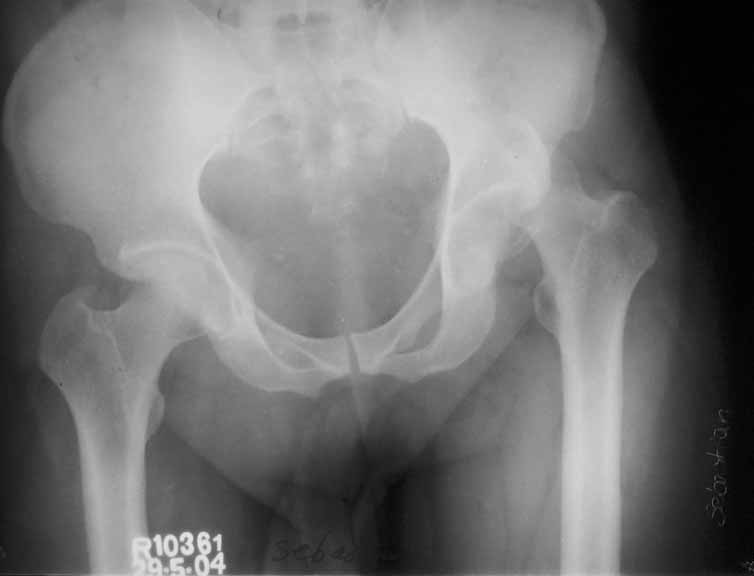

Middle aged adult hospital employee invoved in a road traffic accident. Suffered closed hip dislocation left side and fracture both bones right forearm(ulna compound) Underwent closed reduction of right hip and debridement with ORIF of forearm. Pre op X-ray showed acetabular rim fracture and post op X-ray showed a suspicious fracture line through the head of femur. One fragment of acetabulum seen displaced. CT done subsequently shows an undisplaced fracture through the head of femur with the acetabular rim fracture which is displaced.

The femoral head fracture in Dr. George's (unknown age or medical conditions) male patient is essentially nondisplaced, the hip joint is congruent, there is no joint debris, and the wall is peripheral. Leave it alone.